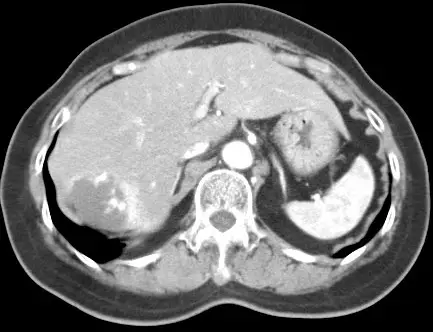

本題提供三張 Dynamic CT 影像,為肝臟右葉 4 cm 腫瘤的三期掃描:

圖一(動脈期 Arterial phase):肝臟右葉可見一低密度腫塊,邊緣出現不連續的結節狀強化(peripheral discontinuous nodular enhancement),強化密度接近血管(aorta/IVC),腫塊中心仍為低密度。